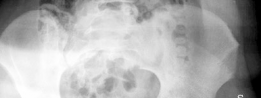

A 20-year-old man is brought to the emergency department following a high-speed road traffic accident in whic…

A 29-year-old man is brought into the emergency department after falling off his motorcycle in wet weather. H…